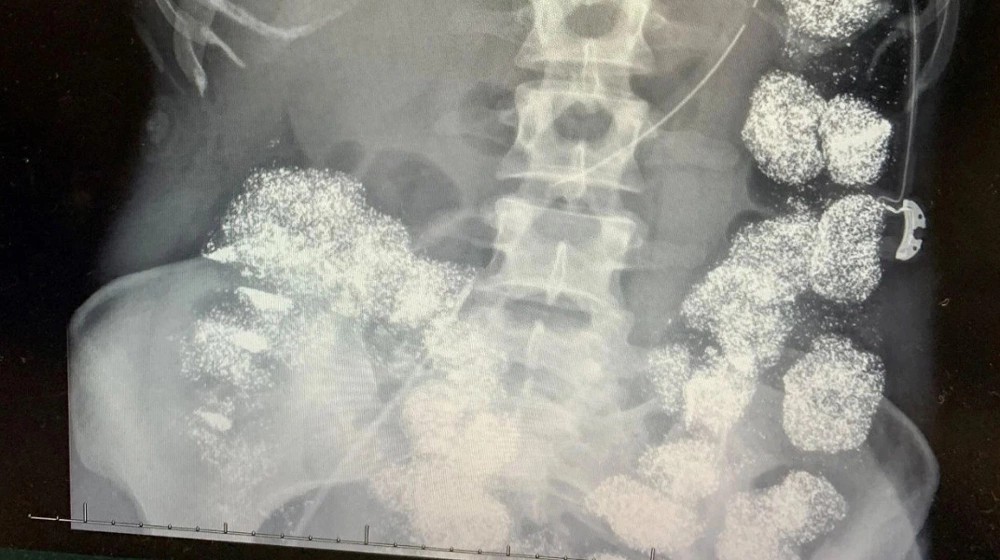

Trong nhiều tháng trước đó, Hannah đã phải vật lộn với những cơn mệt mỏi, rối loạn thần kinh nhưng không một ai tìm ra nguyên nhân. Cô dần tin rằng mình mắc một căn bệnh nan y hiếm gặp và tự trách bản thân. Tuy nhiên, bước ngoặt của vụ việc xảy ra khi kết quả xét nghiệm máu cho thấy một sự thật kinh hoàng: nồng độ chì trong cơ thể cô cao gấp 8 lần mức an toàn cho phép. Hình ảnh X-quang còn gây sốc hơn khi kim loại nặng đã phủ kín dạ dày, đại tràng và ngấm sâu vào xương của cô.